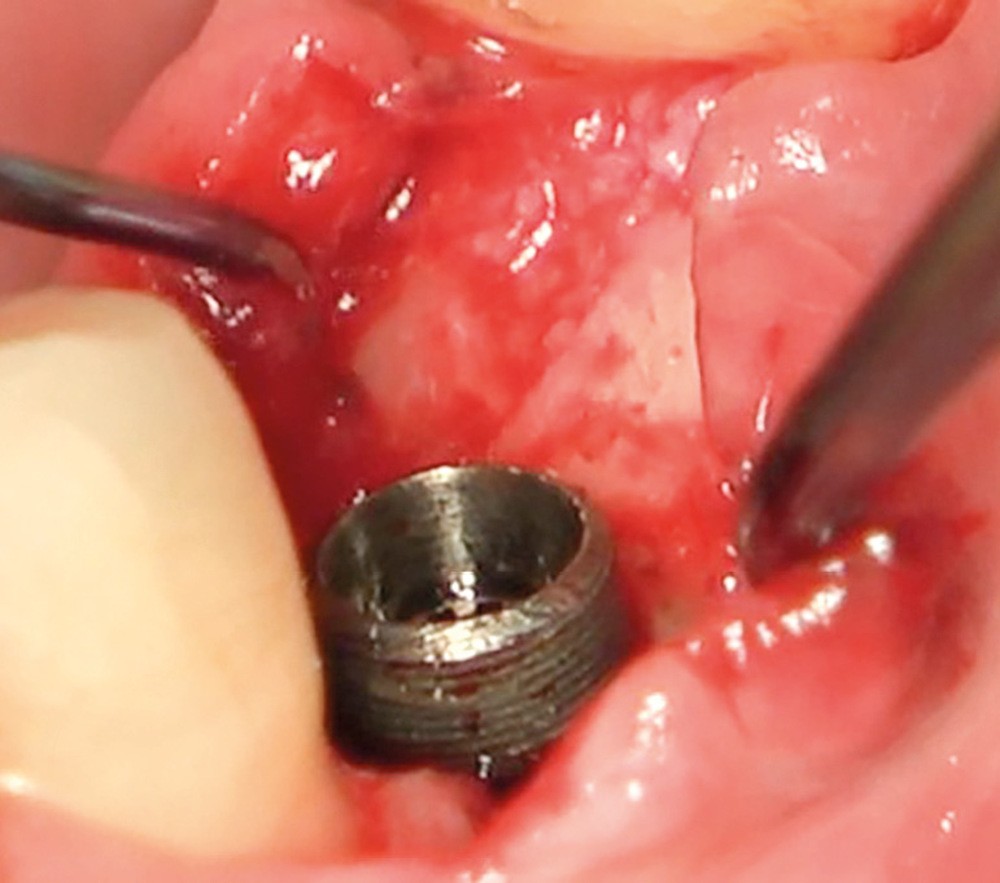

Chez ce patient, le traitement de la péri-implantite a comporté une chirurgie associant décontamination électrolytique de la surface implantaire, régénération osseuse guidée et enfouissement de l’implant. Le résultat à 2 ans est très moyen au vu du pourcentage de régénération osseuse obtenu. Comment peut-on prévoir un tel résultat alors que l’on a suivi les recommandations à la lettre, que l’on a utilisé les dernières technologies de décontamination, que l’on y a mis tous les moyens, que le patient est en bonne santé générale et qu’il vient en plus régulièrement aux séances de thérapeutique de soutien ? Le succès du traitement des péri-implantites n’est pas simple à obtenir, surtout quand un élément clé est compromis… la maintenance personnelle ! En effet le succès n’est possible que si le contrôle de plaque quotidien est optimal et, ici, ça n’était pas le cas. Le patient se brossait certes les dents, mais ne passait pas quotidiennement les brossettes, ce qui…